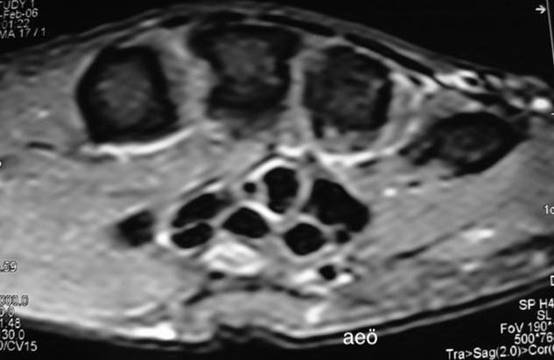

Şekil

2a. El bileğinin kesit

anatomisi (U: ulnar sinir, UA: ulnar arter, FR: fleksor

retinakulum, M: median sinir, H: hamatum,

C: capitatum, Tpzo: trapezoideum, Tpzi: trapezium).

2c. Akut karpal tünel sendromu saptanan hastanın el bileği MR

görüntüleri. Median sinir ödemli ve kalınlaşmış olarak izleniyor (ok).